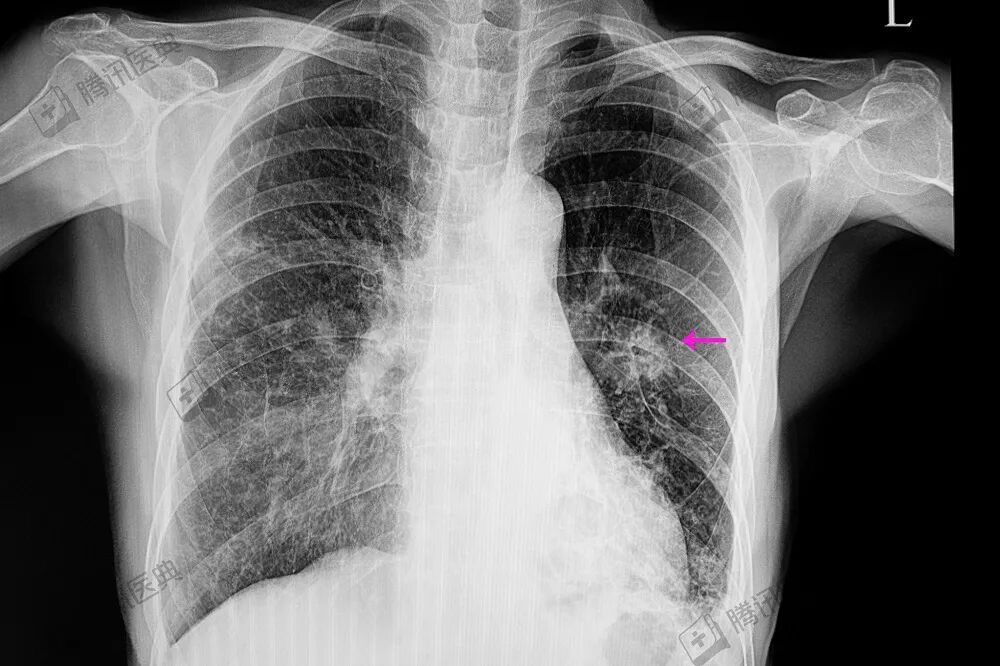

2020年4月,距离松松发病已一年,他肺里的结节突然增大,从0.4厘米到1厘米多,发生了肺肿瘤转移。

随着病情加重,松松要靠胸部插管排气、排液,两肋一边一根管子,否则就喘不上气,不吸氧血氧就迅速掉下来。

“他一半多的肺不工作了,呼吸只靠一侧。”孙淑琴说。反反复复7次胸部拔管插管的疼痛,让松松非常恐惧,吴喜飞和孙淑琴两人心疼,但手足无措,他们都明白,儿子的病已经没救了……